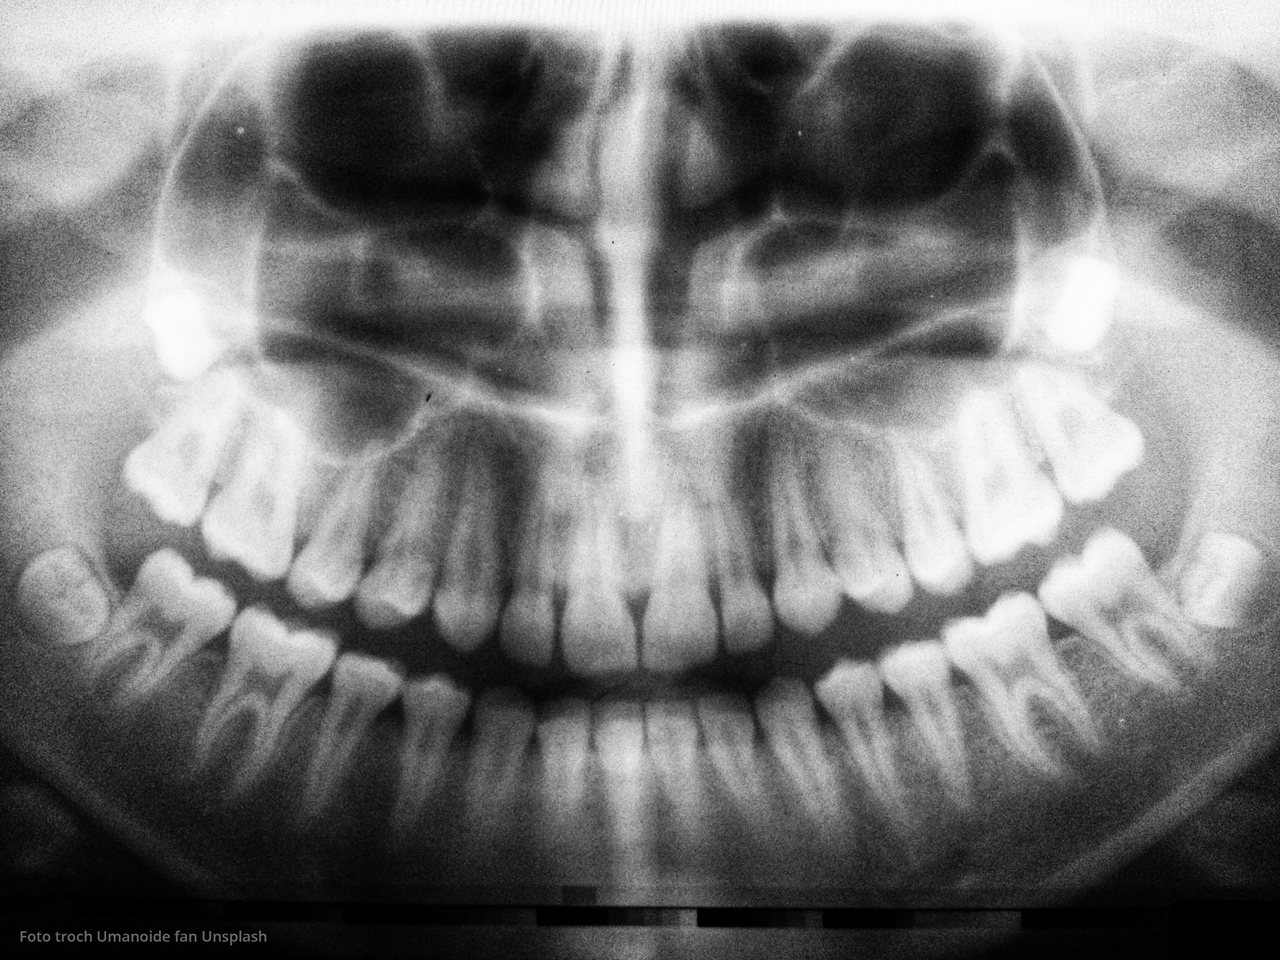

Sûnder reden, gjin hurde nùtsjeboel as sa, falt er in fulling ùt myn kies. In pear dagen letter noch ien, en omdat ik grutsk bin op myn eigen gebit meitsje ik my der soargen oer.

Ik sis, ‘Yn in âldereinhûs. En ik ha twa losse fullingen.’

Myn soan kaam thûs, en krige tafollich itselde ungemak mei syn gebit. Mar hy koe daliks holpen wurde (..).